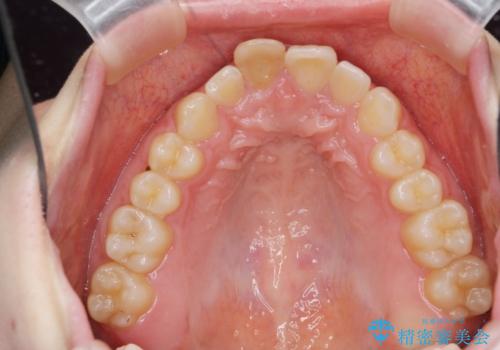

前歯のがたつき 深い噛み合わせを改善したい

- 「前歯のガタつきをきれいにしたい、噛んだ時に下の前歯が見えないことを改善したい」とマウスピース矯正を希望され来院されました。

マウスピースに加え、矯正用マイクロインプラントやゴムを併用し、がたつきや噛み合わせの深さを改善していきます。

ゴムかけやマウスピースの装用時間、しっかりとマウスピースをはめ込むチューウィーをしっかりと使用したことで良好な治療結果を得ることができました。